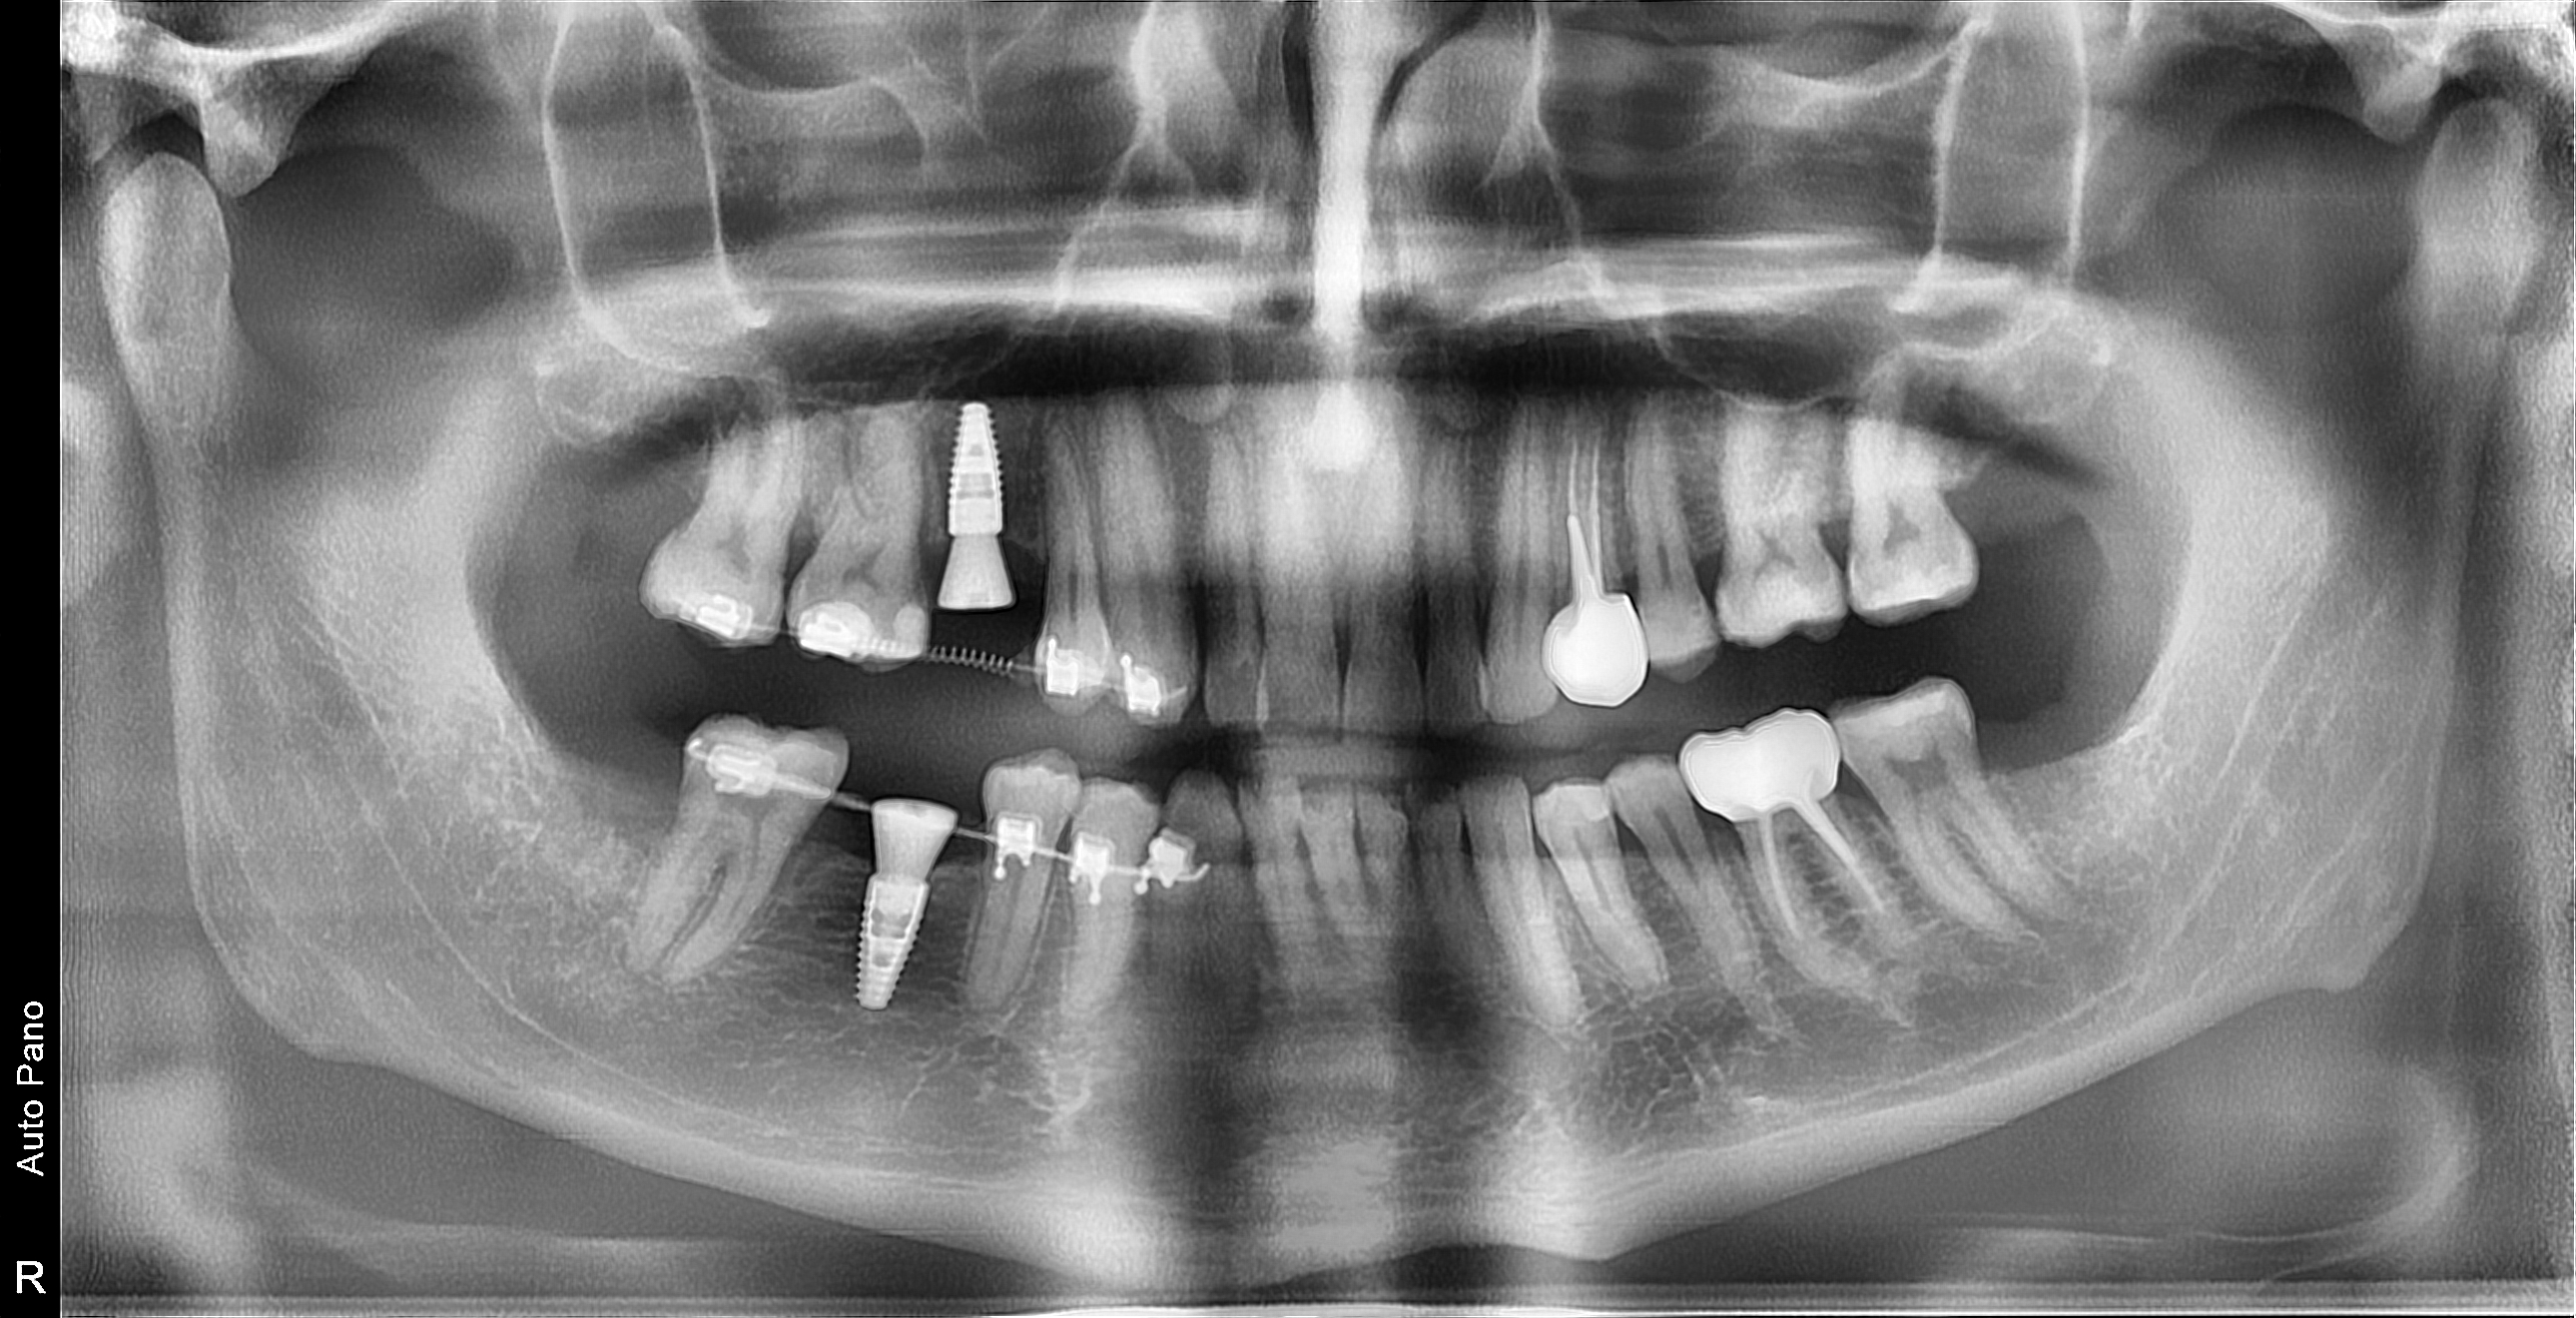

- Планирование и функциональна реабилитация пациентов с полным отсутствием зубов с применением дентальных имплантатов.

- Дентальная имплантация в полном объеме в том числе при сопутствующей патологии. (одноэтапная и двухэтапная методики; непосредственная и отсроченная нагрузки). Использование хирургических шаблонов.

- Восстановление объема костной ткани щадящим способом по методике направленной костной регенерации, как на верхней, так и на нижней челюсти.

- Открытый и закрытый синус-лифтинг с одномоментной и отсроченной дентальной имплантацией.

- Хирургическое лечение одонтогенных кист челюстей малого и большого размеров (цистэктомия и цистотомия).

- Лечение периимплантитов